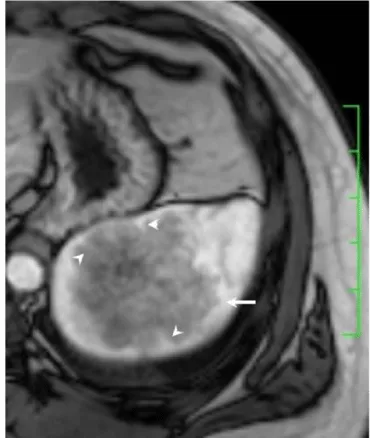

Solitary well-circumscribed masses were detected in all the five patients by ultrasound. One mass was of hypoecho, while the remaining masses were of hyperecho with posterior enhancement (Figure 1A). The maximum diameter ranged from 3.0 cm to 9.0 cm. At CT scanning, two masses appeared as hypodense (Figure 1B) and one was isodense (Figure 2A) to the normal spleenic parenchyma. In the two patients who received MR imaging, masses were isointensity at T1 weighted images (Figure 3A) and hypointensity with scattered sign void spots at T2 weighted images (Figure 3B). After intravenous injection of the contrast materials, all the five masses presented circle enhancement at arterial phase (Figure 3C and Figure 4A), while peripheral enhanced node was noted in one mass (Figure 2B). The circle enhancement persisted and radical line enhancement were observed at portal vein phase in 3 cases (Figure 1C) and progressive filling in was seen in two cases (Figure 2C). At delay phase of MR imaging, one lesion showed obvious enhancement with stellate low signal scar in the center comparing with surrounding splenic parenchyma (Figure 3D), while the other demonstrated central and circle enhancement to form a spoke-like appearance (Figure 4B). At delay enhanced CT scanning, two masses were isoattenuation to the surrounding splenic parenchyma (Figure 2D) and one lesion kept as hypoattenuation but with radial enhanced lines and enhanced circle to form a spoke-like appearance.

At pathological examination, all the masses were well demarcated on gross cut surface. A central stellate scar with peripheral interspersed dark brown nodules and the whitish intervening fibrous bands was noted to form spoke-like appearance (Figure 3E), which was well correlated with CT and MR imaging findings at enhancement. Microscopically, these angiomatoid nodules were surrounded by dense concentric collagen fibrous stroma and dispersed stromal cells with oval-to-spindle nuclei and scanty cytoplasm (Figure 3F). The abunden fibrous stroma may result in hypointensity at T2 weighted MR images. Hemosiderin was noted in the angiomatoid nodules (Figure 3G), which might contributed to signal void at T2 weighted MR images.

It usually affects middle-aged adults [6] and it is commonly found incidentally on radiographic imaging, or during operation for an unrelated condition. In present series, the patients are middle-aged adults without any related symptoms and the lesions were detected incidentally at routine ultrasound of health examinations. On ultrasound, manifestations of SANTs are vary widely from heterogeneous echo-texture with hyperechogenic, hypoechogenic, or isoechogenic appearing lesions, which are unspecific [7,8]. CT and MRI can show some characteristic features of SANTs, which include a solitary well demarcated mass with early peripheral enhancemant with radiating lines and progressive enhancement at the delay phase, and hypointens at T2 weighted MR images [2,3,5,9-13]. These features reflect the underlying pathological changes of scattered angiomatoid nodules separated and surrounded by sclerotic fibrotic stroma [10]. In present series, we also observed these characteristic features with well correlation to pathological findings. Circle and spoke-like enhancement can be contributed to fibrotic stroma surrounding and separating the angiomatoid nodules. The sclerotic fibrotic stroma may also result in isodense on CT, isointensity on T1 weighted images and hypointensity on T2 weighted images of MR imaging. The signal void spots at T2 weighted MR images have not been described at other literatures and may be contributed to hemosiderin deposition due to magnetic susceptibilty artifact.